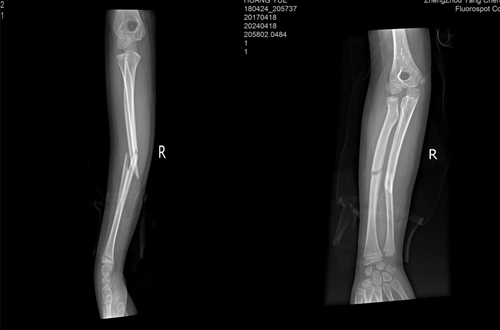

拍片查示

右側(cè)尺橈骨中段骨折

前臂兩個(gè)骨折端移位明顯

(手術(shù)前)